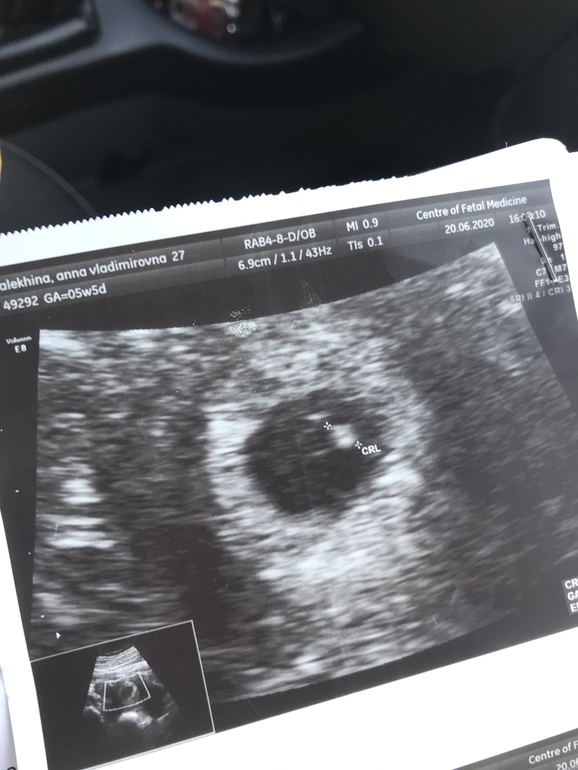

Всё о нашей беременностиПривет! Сходила на второе УЗИ для успокоения.

На срок 5,6 плодное яицо круглое- круглое,

А сейчас 7,2 - овальное. Разве это не тонус ?